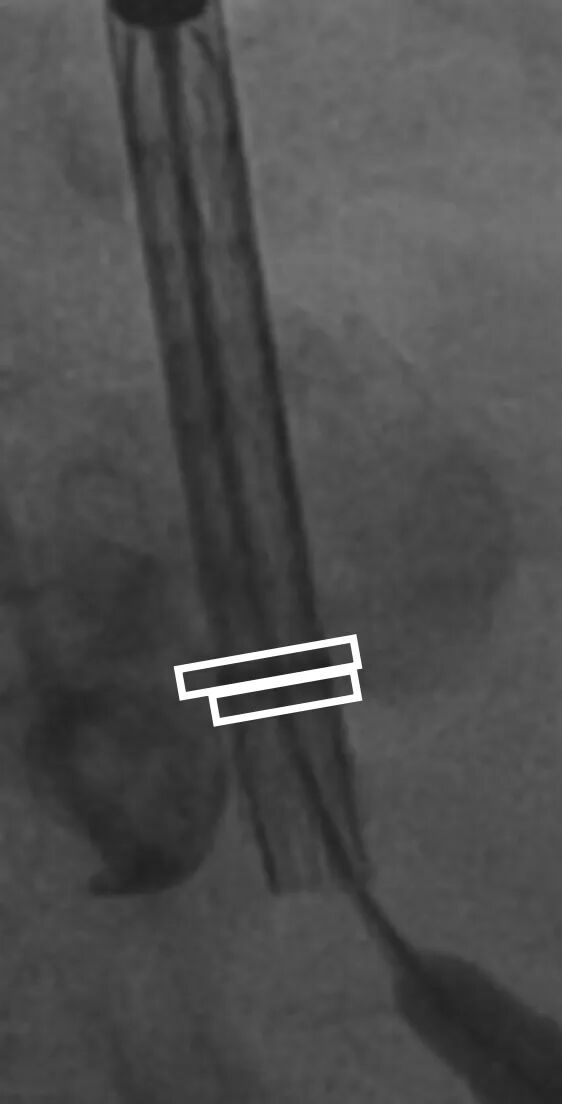

病例概览

患者病史 体检发现心脏瓣膜病半月余,平素无症状 ,有高血压病史。 后来院复查诊断为:主动脉瓣狭窄(重度)、先天性主动脉瓣二叶瓣畸形、心室肥厚、升主动脉扩张心功能 I 级(NYHA 分级)、高血压病 2 级(极高危)。 术前 CT:Type0型二叶瓣,瓣叶增厚,无钙化,类风湿性;瓣环径25.6mm,LVOT稍收窄,瓣环水平夹角66.6°,轻微横位心;左右冠开口高度可,瓣叶不长,无冠脉风险;心室收缩末内径约32mm,室壁增厚;外周入路无明显迂曲,无钙化、双侧内径可、双股中分叉,右侧为主入路能够支持20F大鞘通过。 造影角度及入路:LAO 6° CAU 13° 手术策略 采用右侧股动脉为主入路,左侧为辅助入路,常规穿刺。推荐使用20球囊预扩,预装TAV29瓣膜,初始定位对齐瓣环上0mm开始释放。 手术过程 20号球囊预扩无明显腰征 输送器过弓跨瓣顺滑 80%工作位观察 术后造影,瓣膜释放位置良好,无瓣周漏 术后超声:人工生物瓣释放后形态满意,瓣叶开放、关闭活动良好,无瓣周漏;跨瓣血流速度降至 2.5m/s,平均压力梯度6mmHg,符合手术预期。 Prostyle A®预装干瓣——“刚柔并济”助力临床最优化解决方案: 丝滑过弓能力:Prostyle A®短瓣架设计联合远端超滑亲水涂层,即使没有联合使用snare,都可以柔顺过弓,该例横位心的患者更好的展现了输送系统的柔顺性; 平衡的径向支撑力:该例患者Type0型二叶瓣,术后形态展开良好且无瓣周漏,在横位心等复杂情况下实现稳定锚定。 80%可回收设计:80%工作位观察,起搏时间更短,对患者损伤减少到最小,也利于术中精准调整瓣膜位置,保证术后效果。